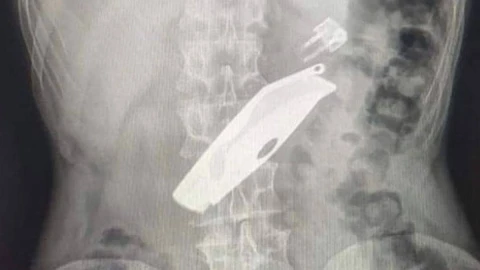

Науқас Уалихан ауданының ауруханасына түнде түсіпті. Оның тыныс алуы нашарлап, сөйлей алмапты. Рентген арқылы ақ халаттылар ер азаматтың ас қорыту жолында тұрып қалған бәкі мен от жағуға арналған шақпақты анықтаған. Бөгде заттар өкпеге ауырлық түсірген. Мамандар отаның бір сағаттан ұзақ жасалғанын айтады. Өз-өзіне келген азамат отбасылық проблемалардың салдарынан осылай жасағанын айтыпты.

"Санавиациямен келген дәрігерлермен бірігіп ауыр ота әске асырылыд. Атап айтсақ, лапаротомия, гастротомия, асқазаннан екі бөгде зат алынды. Қазір науқастың жағдайы орта, ол палатаға ауыстырылды", -  дейді хирург Дәулет Серғазин